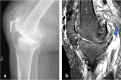

We present a case series comprising three patients with concomitant septic arthritis of the knee and osteomyelitis of the femur. Early advanced imaging rendered the accurate diagnosis of the condition and the appropriate surgical approach and technique used to treat the infection. Repeated extensive surgical debridement, irrigation and insertion of antibiotic-impregnated cement rod into the femur were required, in addition to long term antibiotics. The infection in all three cases was eradicated successfully. Following a period of physical rehabilitation, they had fairly preserved independent ambulatory function. We advocate a high index of suspicion of this condition with subsequent early advanced imaging for a timely diagnosis. In addition, we described our challenges in the fabrication process of the antibiotic-impregnated cement rod.